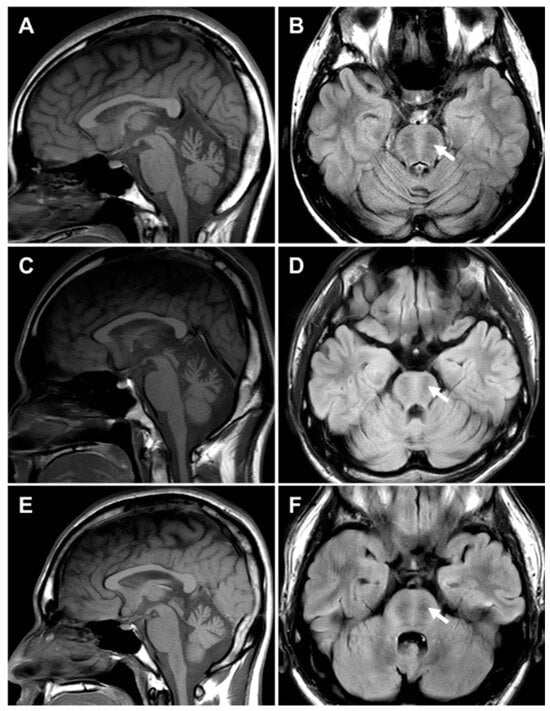

2.5. MRI Features of the Brain and Lower Extremity

4.6. Brain and Lower Extremity MRI

| Brain MRI | NA | NA | NA | Cerebellar atrophy | Cerebellar atrophy | Cerebellar atrophy |